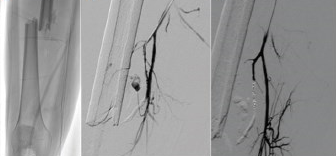

每个病人和每处损伤的治疗选择都应个体化考虑。当严重损伤时手术暴露及/或血管控制较困难时(如在远端股深动脉),倾向于采取经导管栓塞。在这类病例中,手术暴露可能需要分离出供应远端肢体的侧枝血管。在老年患者中,应小心别使这些血管闭塞了。幸运的是大多数肢体创伤的患者为年轻人,没有严重的动脉粥样硬化。 栓塞的技术取决于血管损伤的部位和性质。一般来说,肢体有丰富的侧枝循环。因此重要的是将损伤部位的近端和远端同时栓塞以避免逆向的动脉充盈或侧枝的再灌注。如远端动脉已有血栓形成,则栓塞近端往往即可。对于最外周的分支血管,栓塞损伤动脉的近端部分即可。 有许多材料可用于栓塞。 材料的选择常常和个人偏好和经验有关。在创伤中,暂时性的堵塞物质如明胶海绵理论上很有益,因为大多数病变会愈合。另外纤维弹簧圈尽管是永久性堵塞,但其优点是可以精确的定位。 在肢体中,精确的定位常常是最关心的问题,故更倾向于使用弹簧圈。精确栓塞是指导管头距病变的距离。标准的弹簧圈是0.038英寸或0.035英寸的铁丝或铂丝圈等微弹簧栓子,而微弹簧圈则为0.018英寸或0.010英寸的铂丝圈。这些弹簧圈上覆盖聚酯纤维以增强血栓形成性,可用于多种大小和直的、弯的、复杂的等不同走行的血管。条件是使用微导管。 可脱球囊和组织粘合剂如N-丁基氰基丙烯酸酯可能也有用。但尚未获FDA批准用于该指征。一旦失败可能面临涉诉问题应慎重考虑。无论选择何种材料,都推荐使用动脉鞘维持动脉通路以防栓塞材料黏附在导管内。 栓塞需要在损伤处放置导管。当确定动脉损伤适合于经导管栓塞后,必须将诊断导管送至目标血管。达到合适的导管位置,导管头距离损伤位置1cm左右,为栓塞成功的关键因素。一旦导管到达合适的栓塞位置时,应将一软导丝插到导管尖部以检查其稳定性。若导管稳定,则可使用合适大小的弹簧圈。 ![]() 离重要动脉近端太近的栓塞可能不安全。因为弹簧栓子可能从靶血管逸出导致重要动脉栓塞。若目标血管很小或迂曲,或者诊断导管不稳定,应共轴使用微导管,可减轻血管痉挛,而其稳定性的增加则可使非目标栓塞的危险降低。超选择共轴系统最大程度地保留了血管。 应小心选择适合目标血管的弹簧圈的大小。太大的弹簧圈不会起效,反而会将导管推出目标血管,造成非目标部位的栓塞。太小的弹簧圈则会移到过于远端,可能造成危害其它组织或穿过动静脉瘘,将能栓塞静脉系统,在不适当部位阻塞损伤的血管。 对于动静脉瘘或假性动脉瘤,弹簧圈放置的位置应是使弹簧圈和损伤的血管间没有动脉分枝。故不必要阻塞假性动脉瘤或动静脉瘘本身,而更重要的是损伤部位近端和远端的血管。可先直接将弹簧圈放置于损伤部位远端,然后逐渐往近端放置。开始放置一较大的弹簧圈可为较小的弹簧圈的稳定放置提供支撑。 若损伤动脉的远端动脉为永久开放的或不能从近端血管达到远端的节段,可采用其它的策略以防止远端逆流灌注。 对于假性动脉瘤,可用小的明胶海绵颗粒阻塞远端动脉节段。对于动静脉瘘,可采取经静脉途径或直接经皮穿刺远端动脉来实现 据报道经导管栓塞的成功率为85-100%。用现代的导管和共轴系统可方便地达到这种高成功率。并发症与诊断性动脉造影一样,但多了非目标栓塞。 细致的技术和必要时使用微导管和微弹簧圈可使非靶血管栓塞少见。若弹簧圈未能张开,可有一系列的圈套器将弹簧栓子取出。栓塞后的感染罕见。适当的病变选择和技术不应发生严重的肢体缺血。当使用明胶海绵或弹簧圈而不是那些可达到小动脉或毛细血管水平的物质如明胶海绵粉或酒精时,局部组织的梗死是可以避免的。经导管栓塞是安全有效的,成为动脉损伤的确切治疗方法。 对于那些损伤的动脉不能被阻塞者,手术介入仍是有用的疗法。主要动脉(如股浅动脉)的动脉造影发现大出血时,若临床状况允许,可用阻塞球囊进行短暂的阻塞以减少再转运至手术室过程中的血液丢失。 在一些主干动脉损伤的情况下也可避免手术。支架和覆膜支架的发展增加了经导管治疗的方法,可处理那些血流必经通路上的动脉损伤。这些动脉的栓塞可能不安全。病例报告显示在不适合栓塞的情况下裸支架或更常用的覆膜支架可成功地治疗主干动脉的损伤。裸支架用于治疗假性动脉瘤和外伤性血流限制的夹层。覆膜支架用于某些动脉损伤如锁骨下动脉、腋动脉、供动脉、髂动脉、股总动脉及股浅动脉的动静脉瘘已经证实是安全的。 覆膜支架